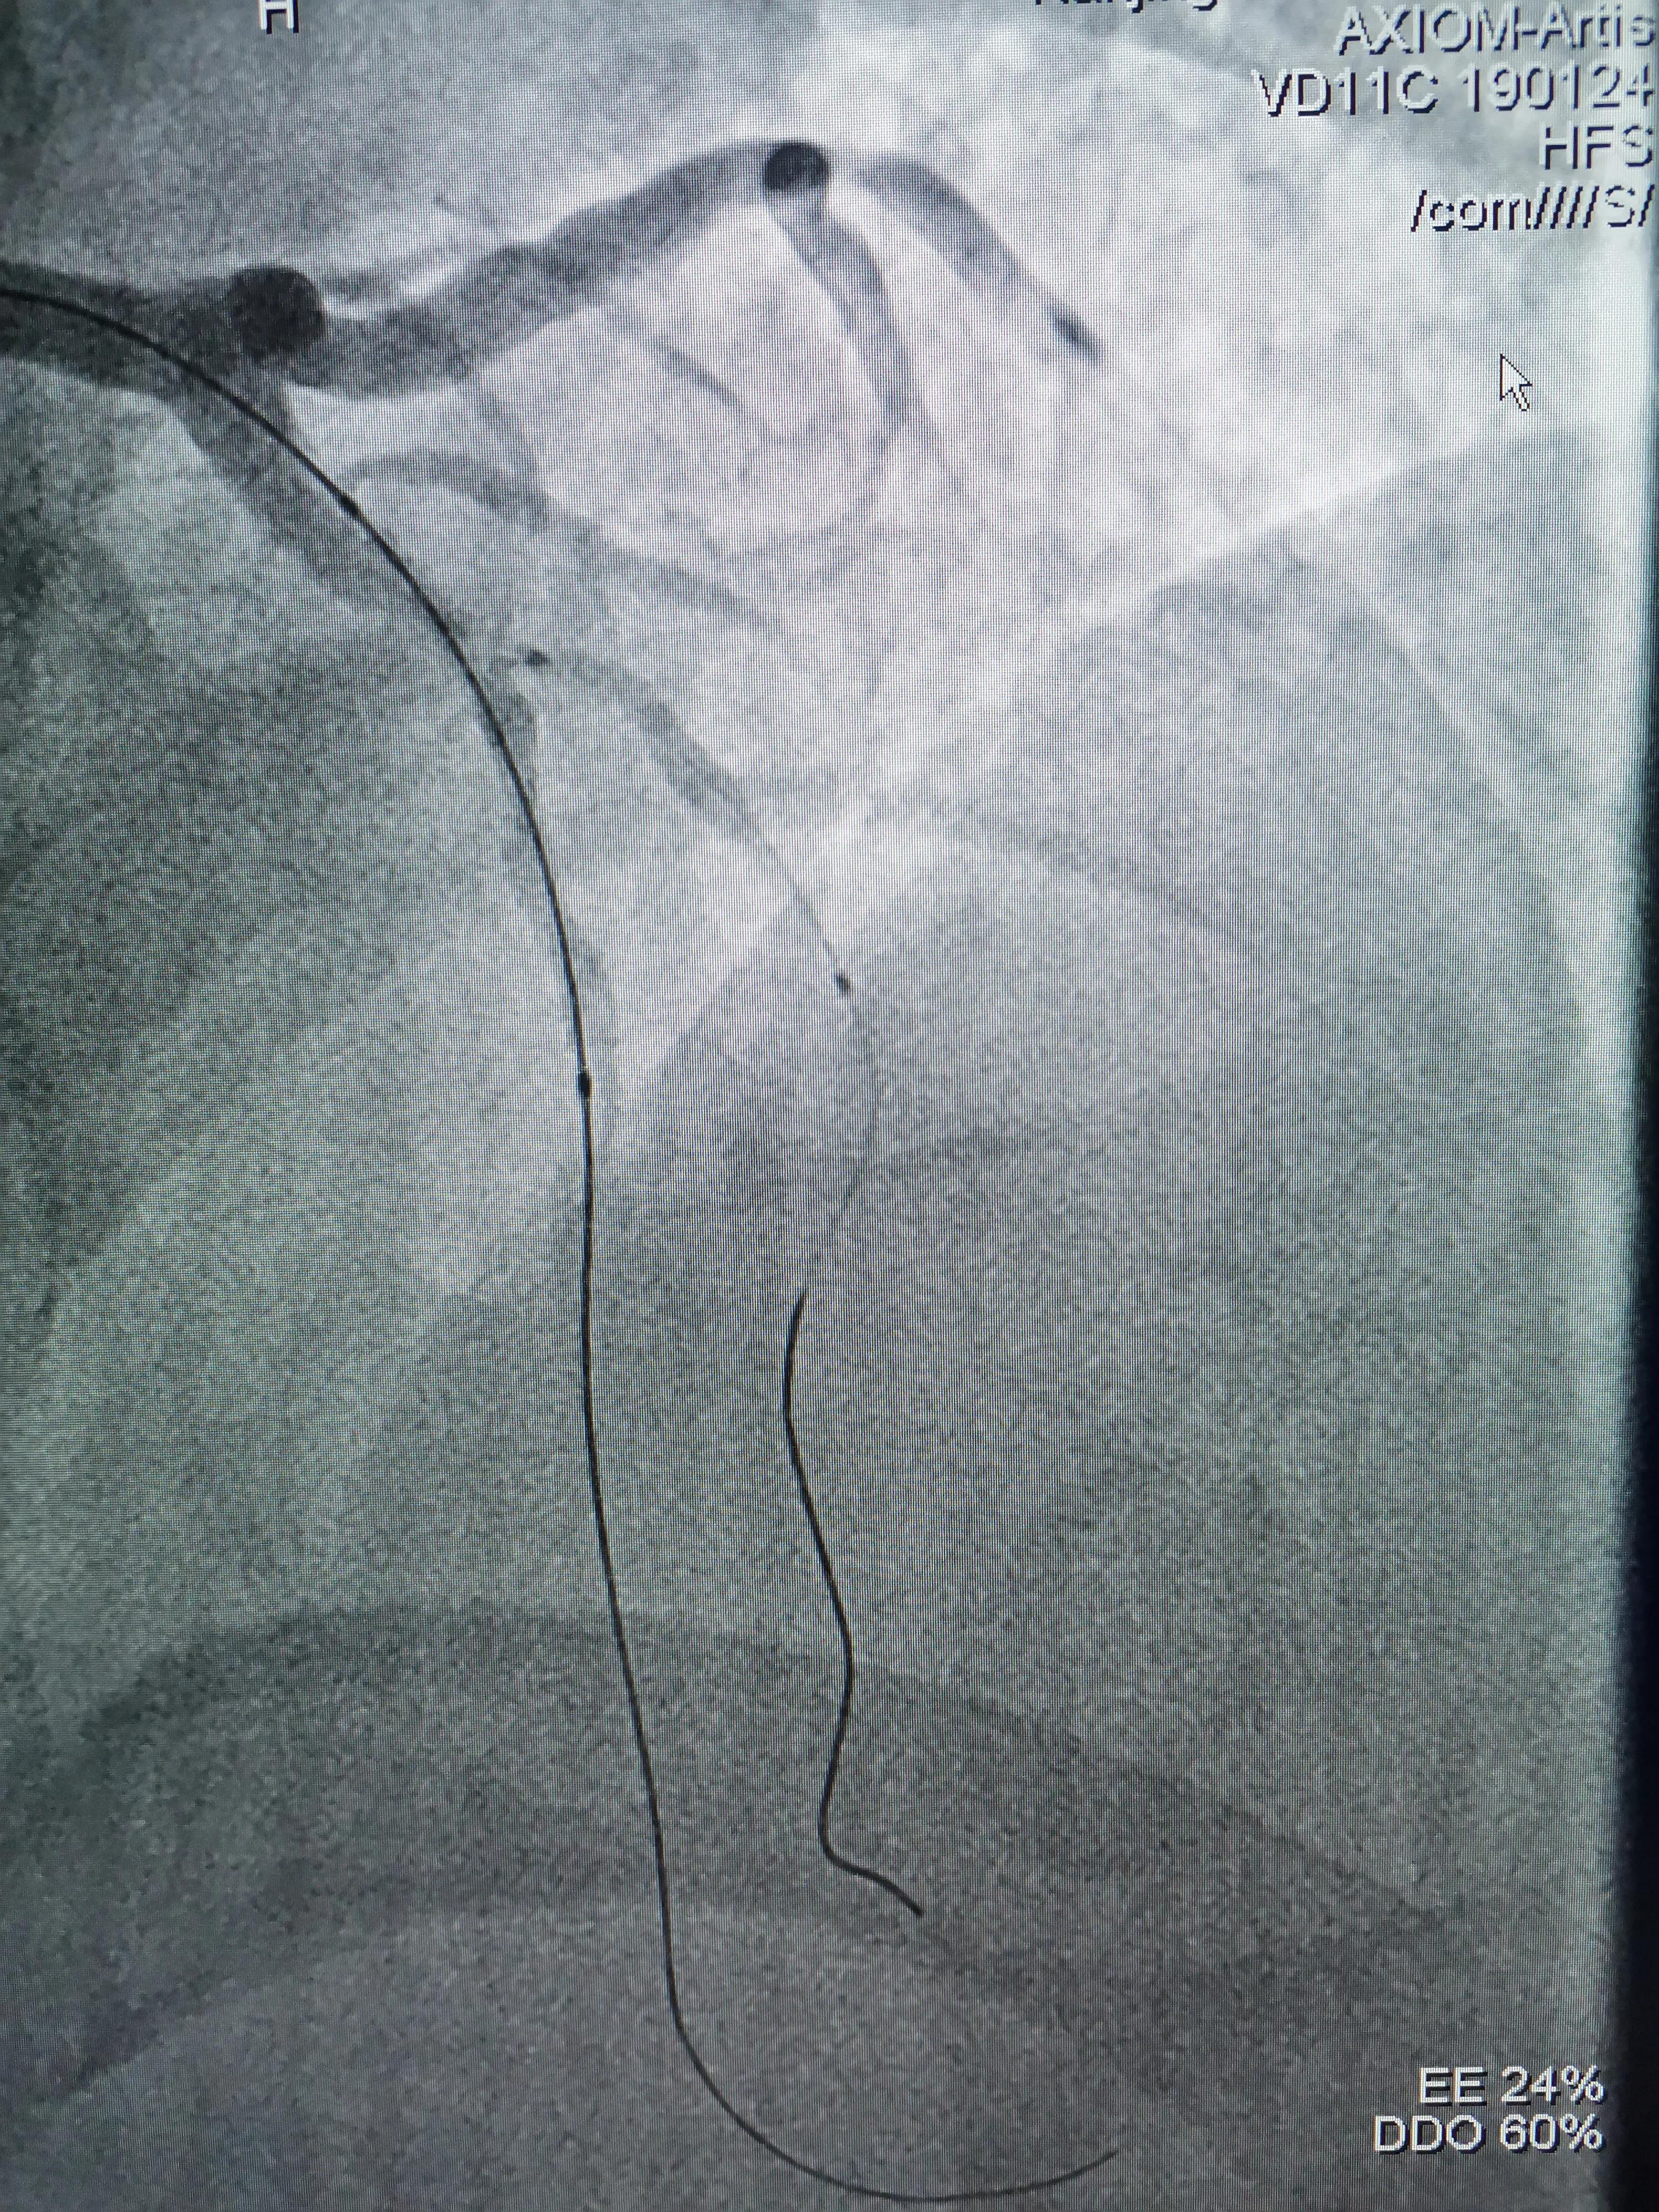

(支架预置LAD近段,D1开口到近段预埋球囊)

(支架球囊扩张,支架释放紧贴血管壁)

(造影发现D1开口明显受累)

(预置在D1球囊在开口处扩张)

(因血管落差较大,支架近段用3.5mm球囊优化扩张)